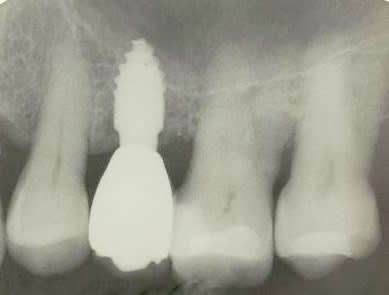

je voulais parler de ce fact pour les implants courts:minimum 4mm os vertical peut suffire (pour eviter un sinus lift externe de tatum) . dans ma pratique depuis quelques années je vois que ca marche , quelques cas cliniques des années passées.

j´ai oublié : 4mm plus 2mm( gagnés par un sinus lift interne)

oui effectivement c est preferable des implants pas agressifs, sur la photo 7 on se rends plus compte que la pointe est plate...